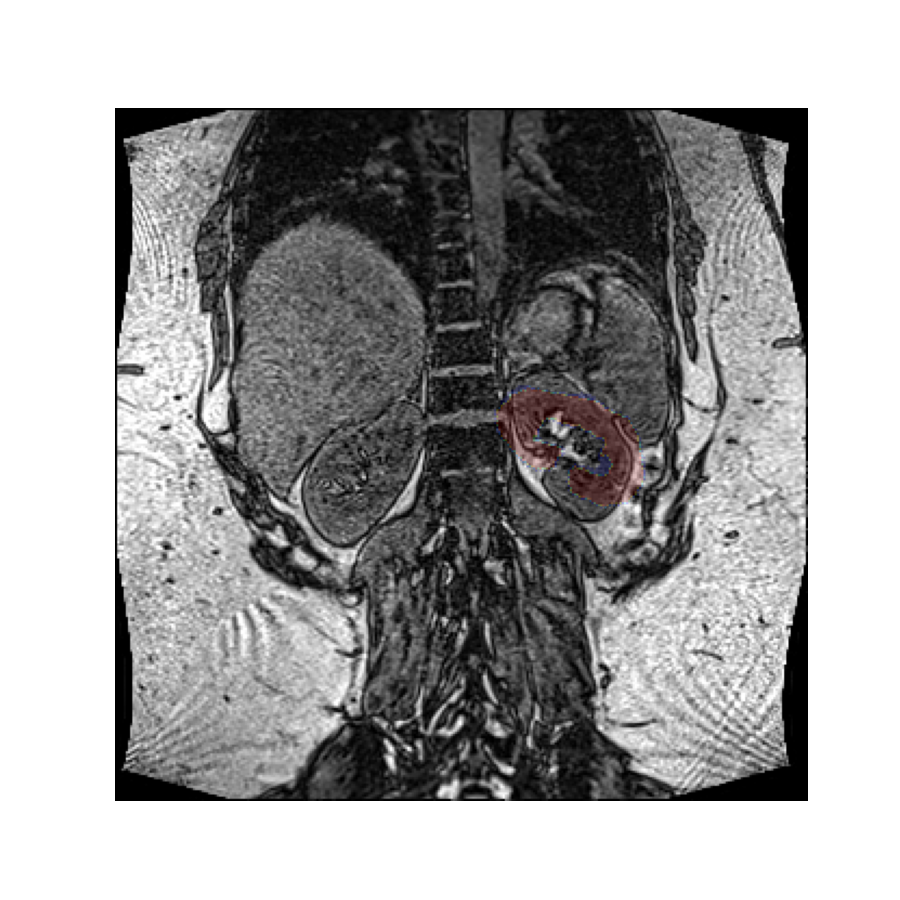

Since we have not specified a rotation center, the rotation was performed around the origin of the volume’s reference frame, which is the top left-hand corner in this image. If we want a different rotation center, we can specify that in the call to the rotation function.

Let’s perform this rotation again, but now rotating around the center of mass of the left kidney. Since the rotation vector is expressed in the coordinate system of the image, we must do the same for the rotation center.